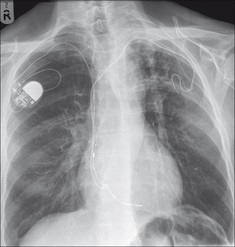

Some pacemakers have three electrodes: one in the right atrium, a second in the right ventricle, and a third lead is placed in the coronary sinus (Fig. 12.2). The coronary sinus lead paces the left ventricle. This system is referred to as biventricular pacing.

Figure 12.2 The position of the coronary sinus opening (red) into the right atrium. The sinus is approximately 3 cm long and runs in the AV groove on the posterior border of the heart. The coronary sinus is the vessel which transmits most of the venous drainage of the myocardium. The site of the foramen ovale is shown in blue.